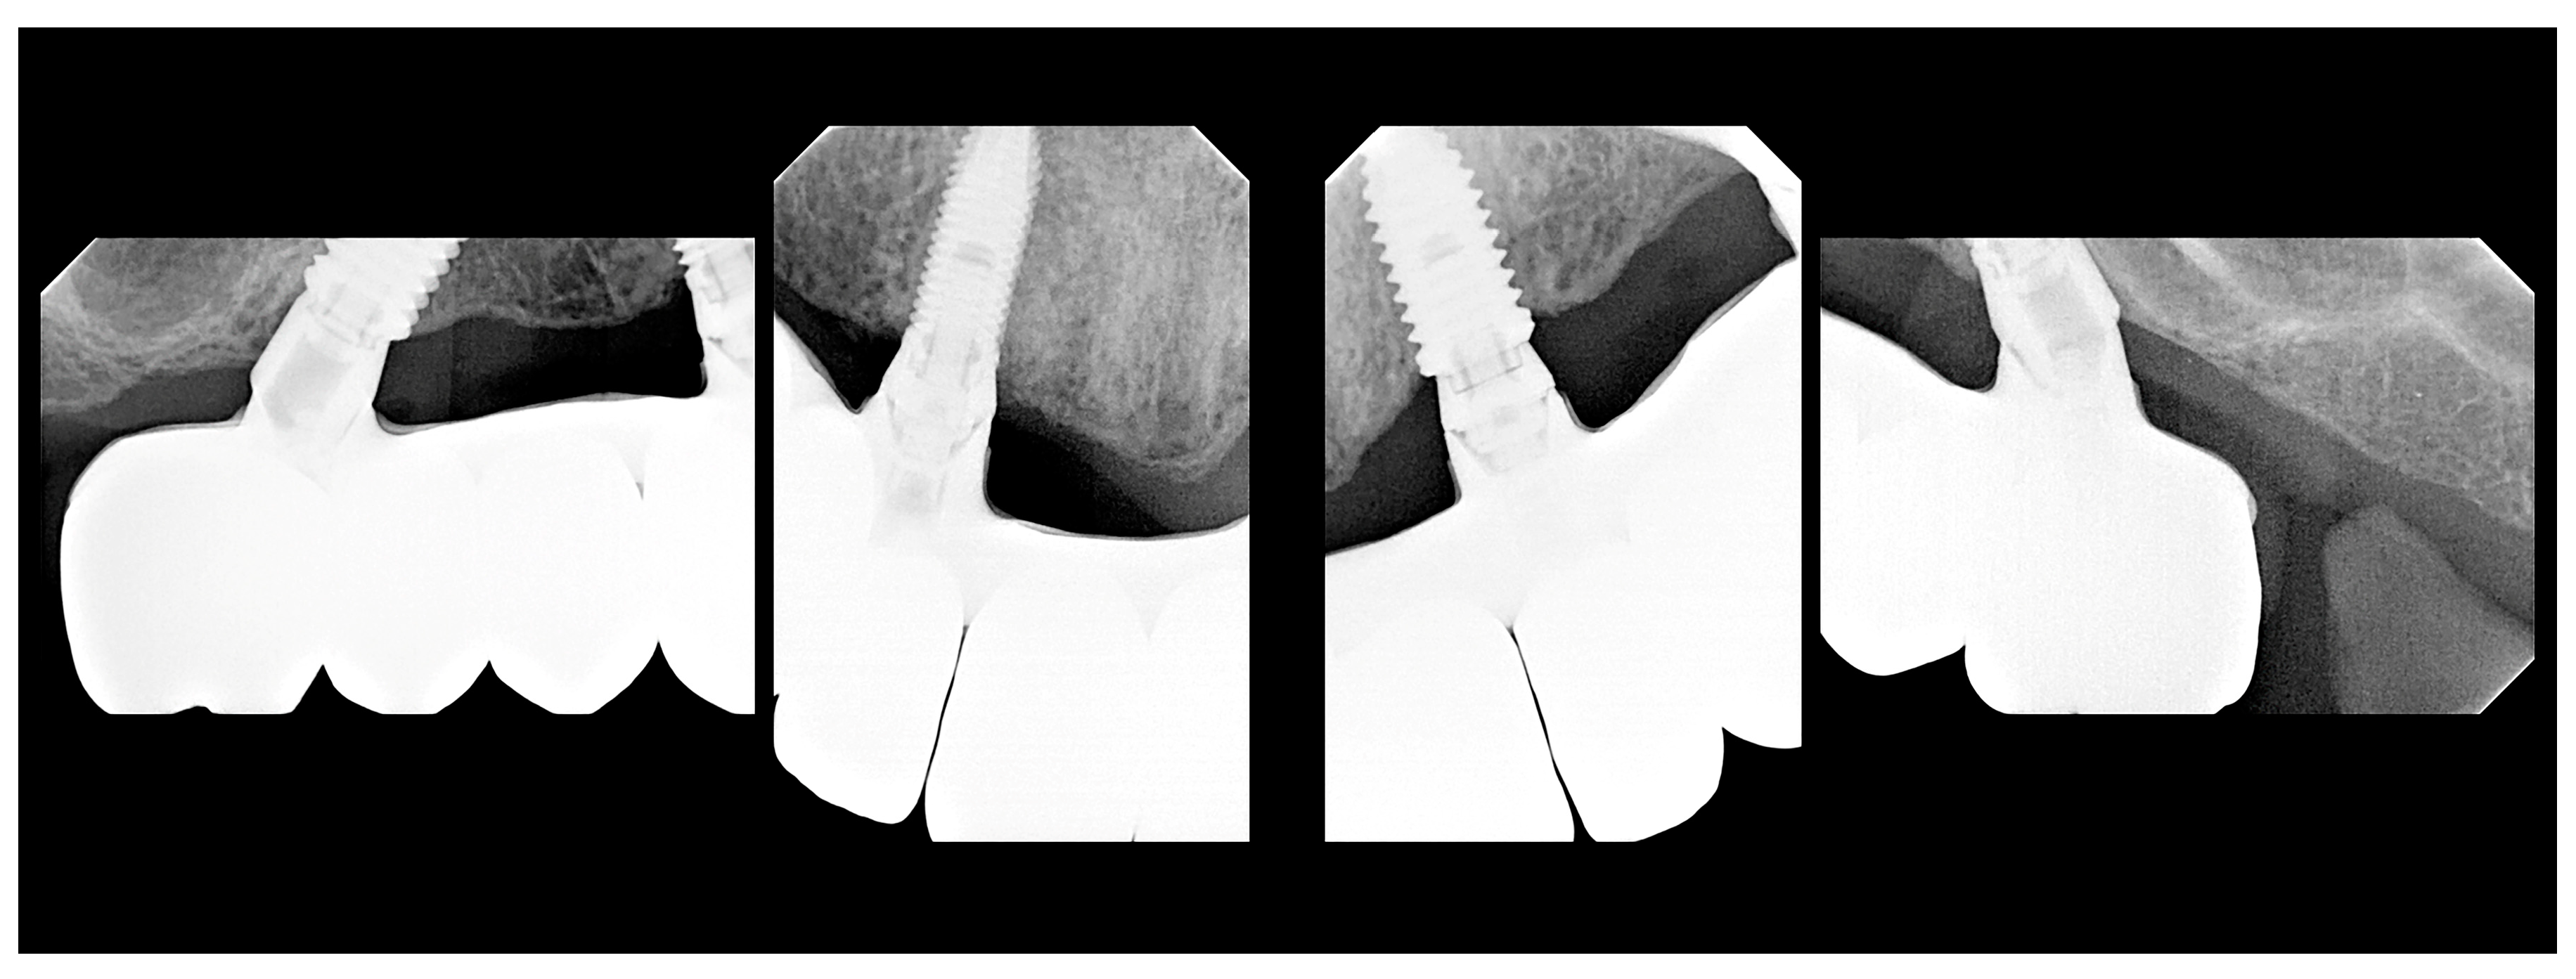

Description of the Technique

3. Results